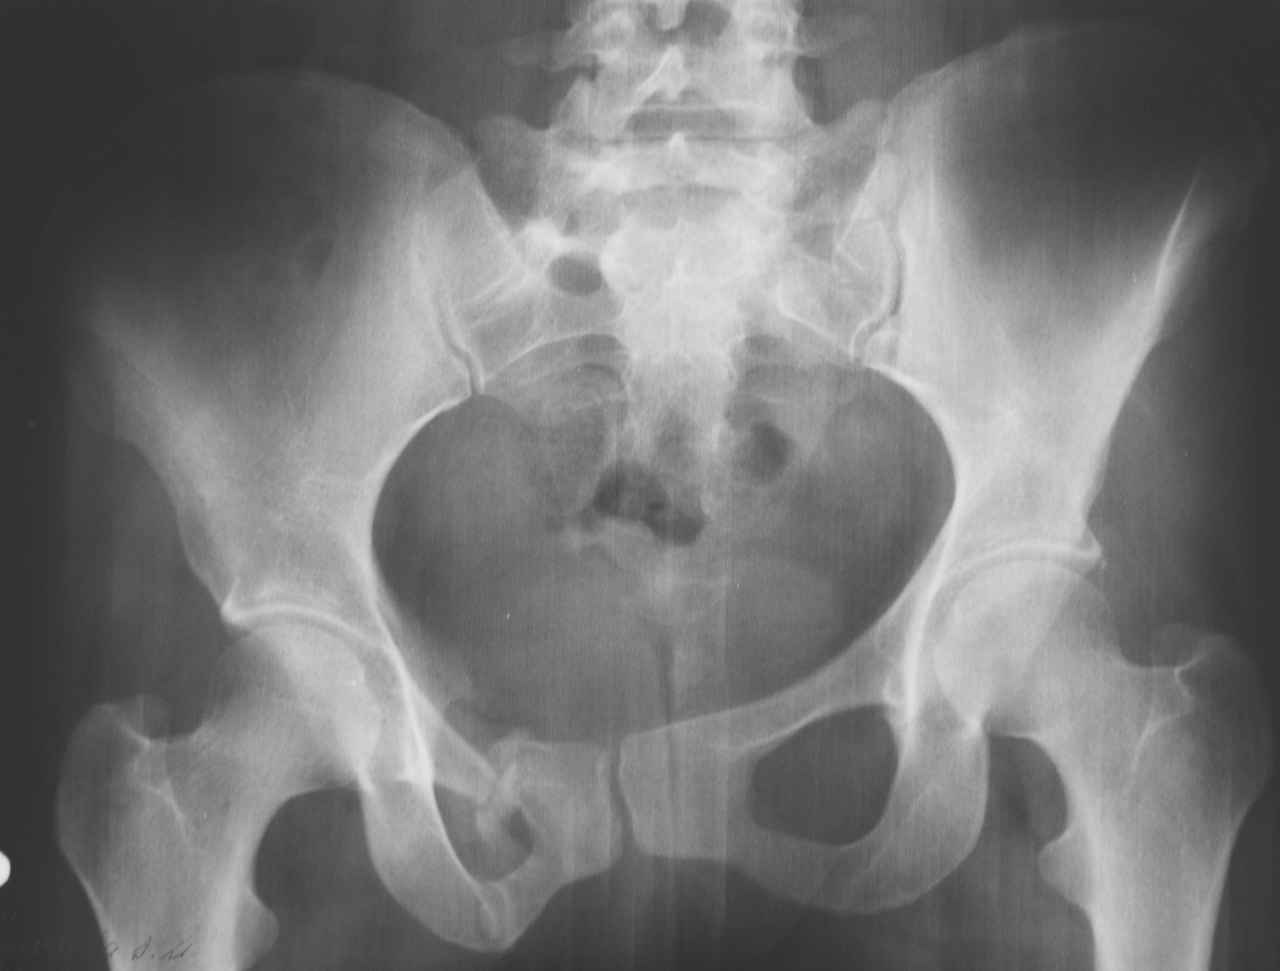

13/03/03 |  13/03/03 |  13/03/03 |  15/09/06 |  15/09/06 |  07/03/07 |  07/03/07 |  19/12/06 | К нам в клинику поступила пациентка 30 лет с диагнозом: Постравматическая ротационная стабильная деформация тазового кольца. Относительное укорочение левой н\конечности на 1 см. Левосторонний компенсаторный сколиоз 2 ст. Болевой синдром. травма автодорожная в январе 2003г. Пассажирка переднего сидения ваз 2109. лечились положением по Волковичу. С марта 2003 года жалуется на боли в тазу, ппояснице усиливающиеся при движении.В настоящее время жалобы на боли в области крестца, КПС больше слева, в пояснично-крестцовом отделе позвоночника. неприятные ощущения, щелчок при выпрямлении правого тазобедренного сустава из положения полного сгибания. боли в тазу появляются при ходьбе ч\з 100 м, так же при вставании из положения сидя, после сидения в течении 2-3 часов. при ходьбе более 100 м появпяется зябкость стоп больше справа. ходит при помощи трости в правой или в левой руке. без трости боли появляются сразу после начала ходьбы. пальпация болезненна в паравертебральных точках средне-грудного и пояснично-крестцового отделов позвоночника, КПС с обеих сторон. Объем движений в тазобедренных суставах полный.правый КПС заблокирован. симптомы натяжения с обеих сторон отрицательны.С 2003г. лечится консервативно, получала ЛФК, массаж, физиолечение - без эффекта. в 2005г. лечилась в санатории с ортопедическим уклоном, получала плавание в минеральной воде, магнитотерапия, массаж, ЛФК. отмечала умеренное улучшение в течении 2 недель.Вопросы:надо ли оперировать, т.е. устранять относительное укорочение левой н\конечности и как?Если не оперировать, то как лечить консервативно?Р-граммы, КТ прилогаются.

Проблема Вашей пациентки находится на границе интересов специальностей ортопедия (вертебралогия) и неврология (нейрохирургия), вероятно, поэтому так мало откликов на ваше обращение. Представленные рентгенограммы не все информативны (особенно спондилограммы от сентября 2006 года). Вероятно, необходимы дополнительные методы исследования к.т. МТГ, ЯМРТ, миелография.

Уважаемый Алексей. Описанные Вами клинические проявления указывают на нестабильность левого крестцово-подвздошного сочленения. Такие больные встречаются не редко (за последние 6мес.в нашей клинике оперировано 3 больных со сроками давности от 6мес. до 1 года). К сожалению рентгенологически их трудно обьективизировать. На КТ это проявляется артрозом и костными разрастаниями КПС. В Вашем случае рентгенограммы и представленные томограммы ничего не дали. Можно попробовать посмотреть связочный аппарат КПС на МРТ хотя не уверен что Вы получите окончательный ответ. Если Вы будете убеждены в этом диагнозе то выход один костно-пластический артродез левого крестцово-подвздошного сочленения с фиксацией канюлированными шурупами. Заманчиво конечно и устранить ротационное смещение половины таза, но это на Ваше усмотрение.

почему она должна возникнуть? Сломан вроде крестец, хотелось бы посмотреть функциональные снимки таза.

Уважаемый Максим. Снимки от 7.03.07 и есть функциональные, т.е. стоя на правой, и левой ноге.